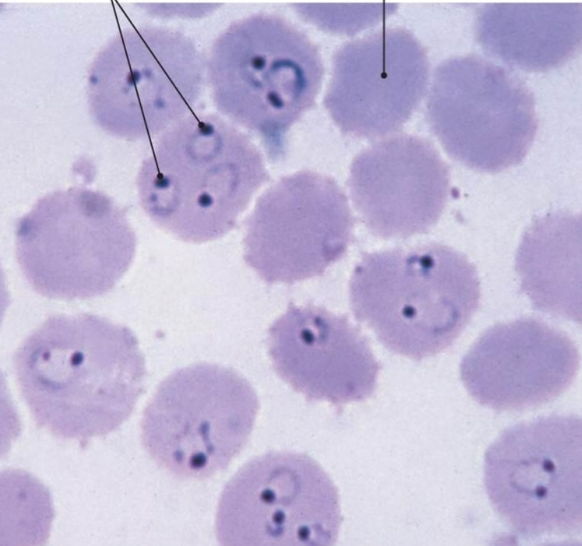

Plasmodium falciparum

Plasmodium falciparum

Plasmodium falciparum